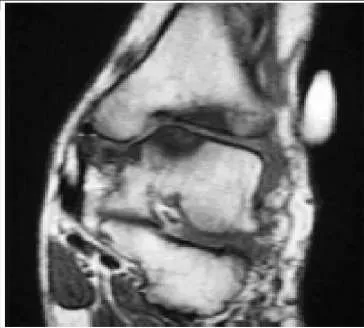

Question 26:

A 76-year-old man has experienced aching in the anterior aspect of his ankle for 6 months. He felt a sudden onset of soreness 6 months ago. Since then, he has noted weakness of the foot. He walks with a limp, and the foot hits the ground during the heel contact phase of gait. On examination there is a mobile subcutaneous mass in the anterior ankle. The patientâ s magnetic resonance image (MRI) is presented (Slide). Which of the following is the most accurate diagnosis:

Correct Answer: A rupture of the anterior tibial tendon

Explanation:

This MRI presents the typical appearance of an anterior tibial tendon rupture. There is no continuity of the tendon distally, and the retracted tendon end has formed a scar palpable as a subcutaneous mass. The clinical history of the weakness associated with a drop foot gait is characteristic of the tendon rupture.